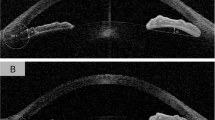

This cross-sectional study included individuals aged ≥40 years with an open angle and underwent anterior segment optical coherence tomography under light and dark conditions from the follow-up cohort of the Handan Eye Study. Ocular data from the right eye were analyzed. The Pearson correlation coefficient was used to assess the relationship between age and iris parameters, including iris thickness (IT), IA, and iris curvature (IC), as well as the pupil diameter (PD) in the dark, and their changes from light to dark conditions. Linear regression analysis was performed to identify the potential factors associated with IA change.